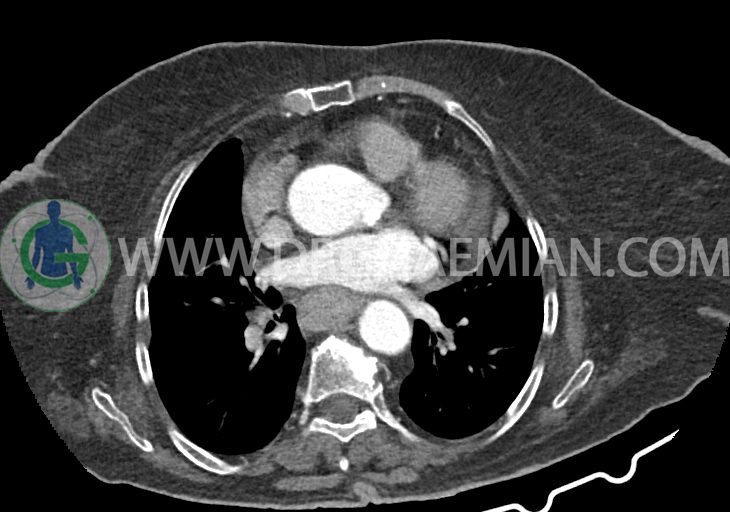

در سی تی اسکن اسپیرال ریه و مدیاستن – شکم و لگن با و بدون کنتراست خوراکی و وریدی (مولتی دیدکتور 16 با مقاطع ظریف و بازسازی های ساژیتال و کرونال):

–کاردیومگالی همراه با pericardial effusion خفیف

–آئورت صعودی دیلاته به قطر 38mm

–لنف نودهای non significant مدیاستینال با حداکثر SAD=6mm در فضای پره کارینا